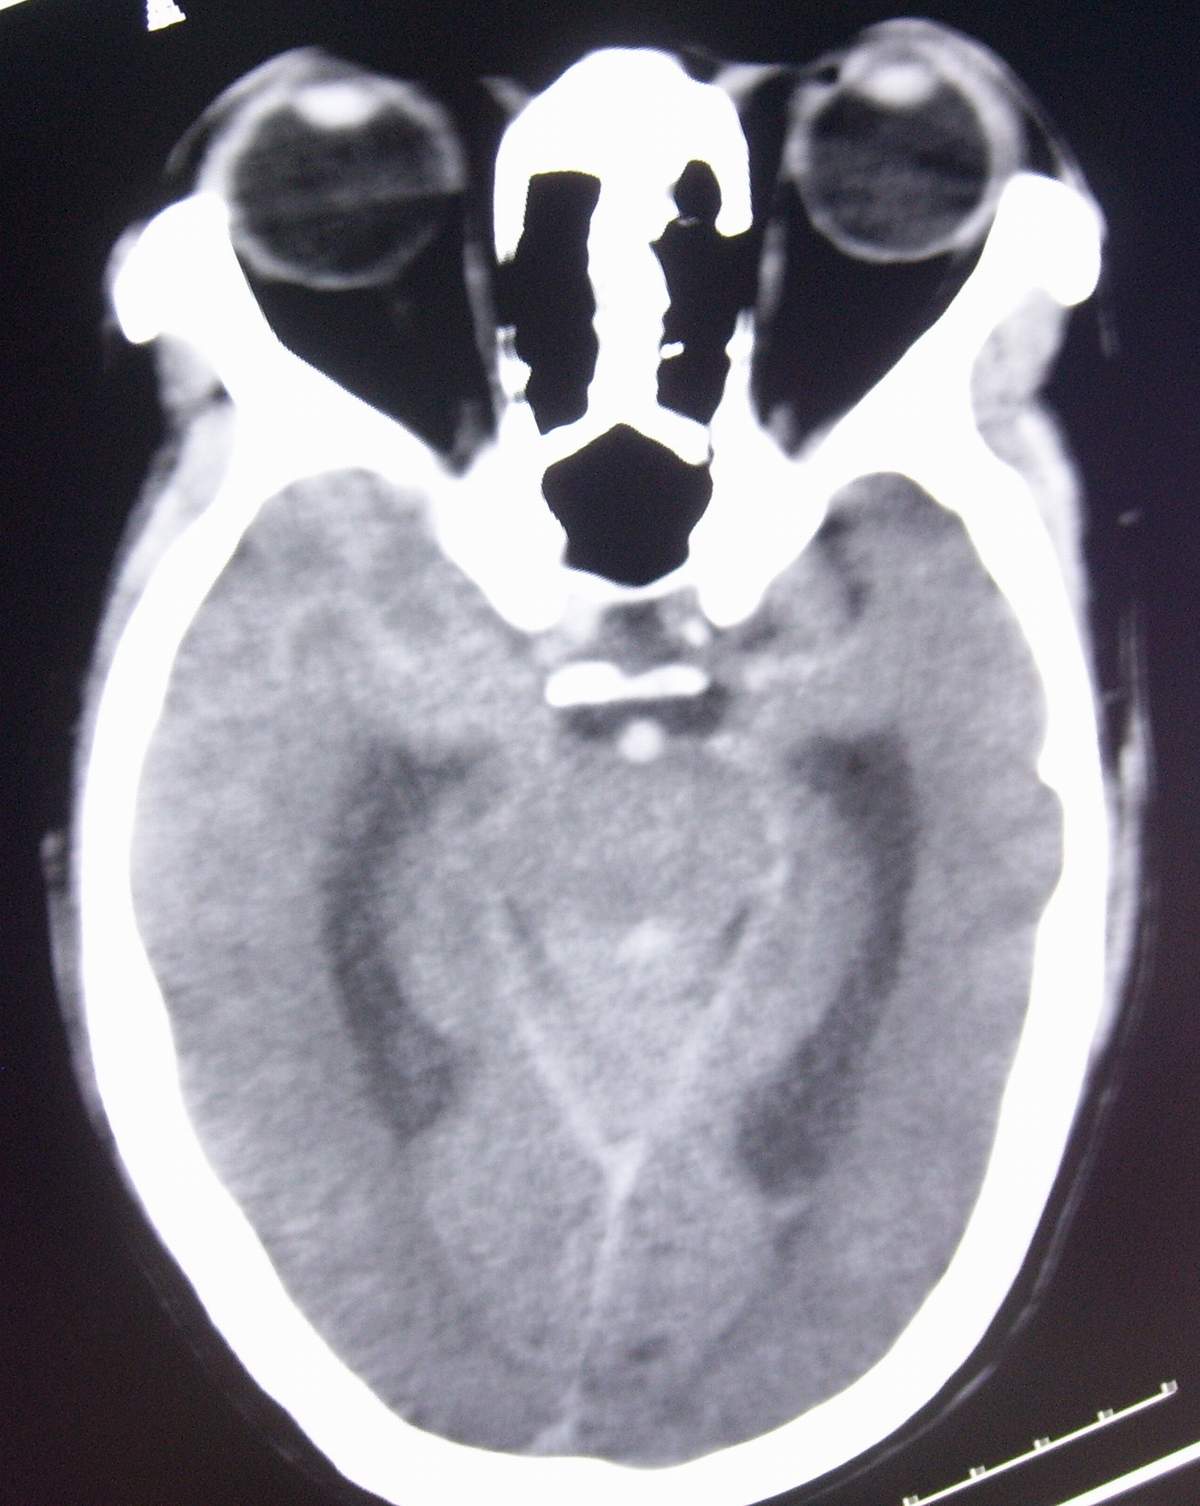

男,55岁,突然不省人事2小时。

小脑出血破入脑室

小脑出血,蛛血

还是支持第四脑室出血可能性大。蛛网膜下腔出血。

考虑脑桥基底部原发性脑出血并破入中脑导水管、四脑室及蛛网膜下腔。

支持右侧小脑半球原发性脑出血破入脑室系统、蛛网膜下伴急性梗阻性脑积水。

右侧小脑出血并破入脑室系统、蛛网膜下腔

考虑小脑出血破入脑室系统,蛛血.

考虑小脑出血并破入脑室,急性梗阻性脑积水;

支持小脑蚓部出血伴脑室及蛛网膜下腔积血。脑积水。进一步查因。